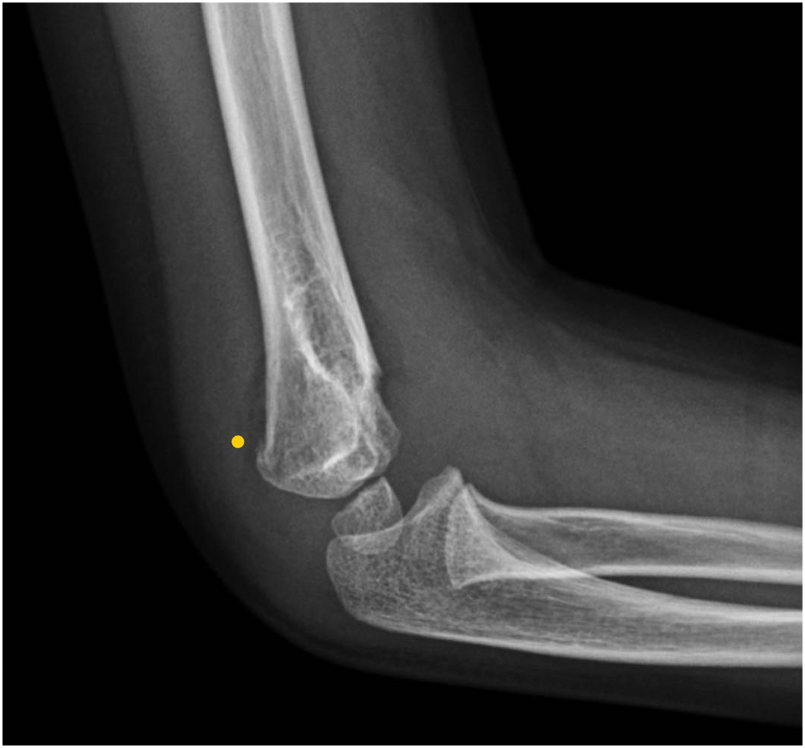

在过去两年中,患儿发生了三次上肢骨折:右侧(图1)和左侧(图2)肱骨髁上骨折,以及右侧肱骨内侧髁骨折(图3)。所有骨折均由家中或学校发生的轻度至中度外力创伤所致,且均与体育运动无关。骨折在经过4-5周的石膏固定后愈合,无后遗症。无骨痛、腹痛、排尿或排便习惯改变或其他全身性症状,也无提示儿童虐待的体征。

图2